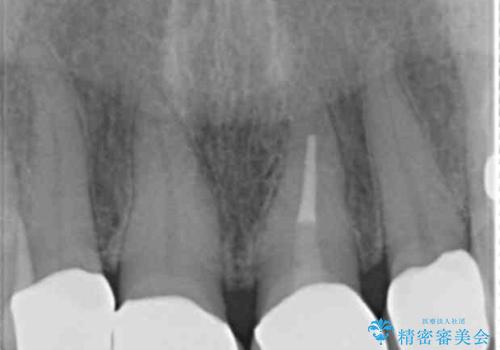

5年前のクラウン装着時と比較したところ、歯肉が成熟し歯間乳頭ができており、より天然歯のように自然に見えました。

患者様の良好なセルフケアと精密な適合の良いクラウンにより、歯肉の腫脹や退縮も認められませんでした。

5年前に行った治療に大変ご満足頂き、他の部位も治療やホワイトニングを希望して下さいました。

人工のダイヤモンドにも用いられるジルコニアは、セラミック系素材の中でも圧倒的に丈夫かつ審美的で、劣化しにくく口腔内でも長期間安定した状態を保つことができます。

クラウンの種類:ジルコニアオールセラミッククラウン スタンダード